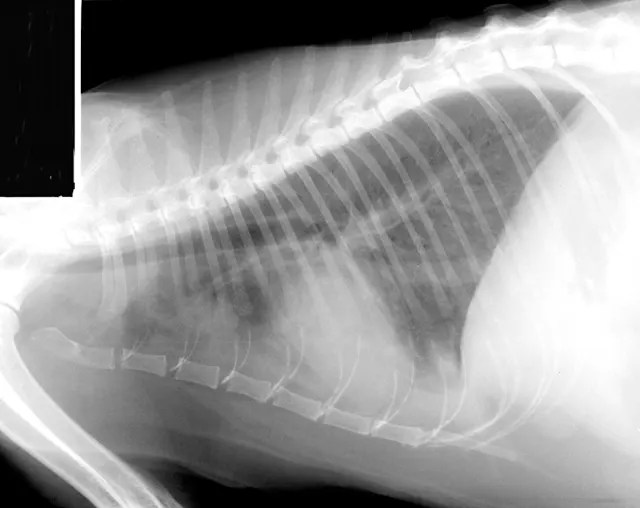

FIGURE 1A

Lateral thoracic radiograph from a cat with heartworm disease. A fine interstitial pattern is noted in the caudal lung lobes, and the chest is somewhat hyperinflated. This radiographic pattern is similar to, and thus can be confused with, that of feline bronchial disease.